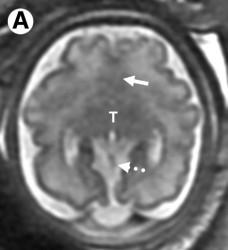

Remember to start with Sweep the Midline… Where is the anterior commissure?

Always finish the sweep looking for second anomaly…

Parallel ventricles

Radial or pallisading gyri in sagittal plane

Colpocephaly

Longhorn or Viking helmit frontal horns

High riding 3rd vent

“Keyhole” temporal horns

Vascular anomalies: “wandering ACAs”

All 3 commissures are absent.

Cingulate gyrus (black arrows) “mirrors” the development of the corpus callosum.

Enlarged HC connects fornices, not cerebral hemispheres